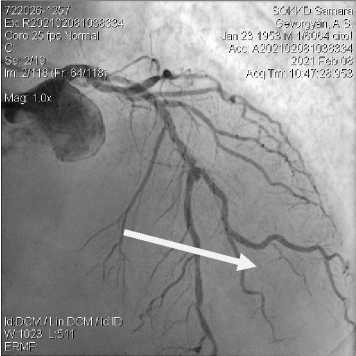

Учитывая полученные данные МСКТ коронарных артерий при отсутствии клинических проявлений ишемической болезни сердца, в плановом порядке выполнена коронарография (КАГ) в условиях СОККД им В.П. Полякова (рис. 4). По результатам проведенной КГ: тип кровоснабжения сердца - правый, определяется выраженный кальциноз стенок артерий, ствол левой коронарной артерии: с неровными контурами, передняя межжелудочковая ветвь (ПМЖВ) - с неровными контурами, стеноз 50% в средней трети 1-го сегмента, осложнённый аневризмой стеноз Medina (1 -1-1) 99-75-99% в проекции крупной 2 диагональной артерии (ДА), этажные стенозы 50% в средней и дистальной трети 3-го сегмента; огибающая артерия (ОА) - с неровными контурами, слабо развита, стеноз 50% в средней трети 2-го сегмента. Стеноз 75% в проксимальной трети мелкой 1 ВТК; правая коронарная артерия (ПКА) - с неровными контурами, без гемодинамически значимых стенозов.

Рисунок 4. Коронарография. Стеноз бифуркации ПМЖВ-ДА. Стрелкой указан критический стеноз ПМЖВ

Figure 4. Coronarography. Permanent residence bifurcation stenosis IN-YES. The arrow indicates the critical stenosis of the pancreas

Рисунок 5. Коронарография. Состояние после стентирования бифуркации ПМЖВ – ДА. Стрелкой указан установленный стент Figure 5. Coronarography. The condition after stenting of permanent residence bifurcations is YES. The arrow indicates the installed stent